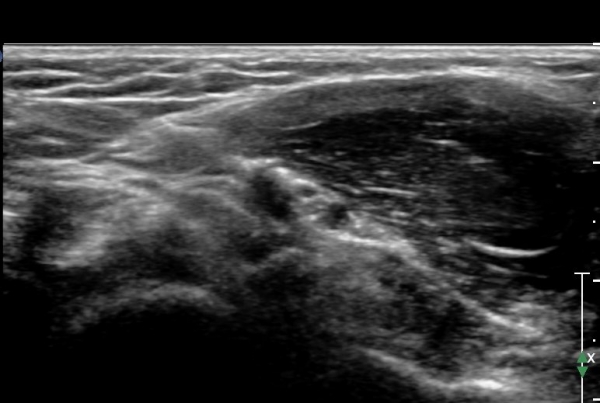

Á¤Á߽Űæ Á¾´Ü¸é°Ë»ç¿¡¼­ ȸ³»±Ù ¿ä°ñµÎ ±â½ÃºÎ¿¡¼­ Á¤Á߽ŰæÀÇ ±¹¼ÒÀû ¾Ð¹Ú°ú Ç¥ÃþÀ¸·Î ÀüÀ§°¡

°üÂûµÇ°í ¾Ð¹ÚÀÇ ±ÙÀ§ºÎ¿¡¼­´Â Á¤Áß½Å°æ ºÎÁ¾ÀÌ °üÂûµÊ(»çÁö 3).

ÀÌ·± º¯È­´Â °ÇÃø(»çÁø 6)°ú ºñ±³ÇÏ¸ç ¶Ñ·ÇÇÔ.